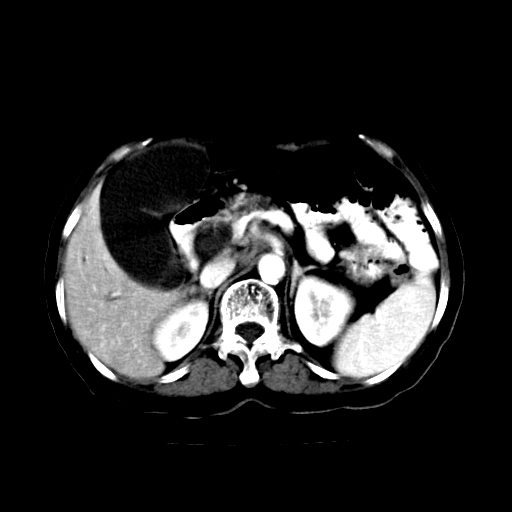

女,74岁,上腹部不适、腹胀两月余,黄染四天。请大家看看肿块周围血管情况。

肝内外胆管增粗,梗阻点位于胰头部,胰头增大,轻度不均性强化(较正常胰腺强化低,胰体尾呈退化';羽毛状';),孝虑为胰头ca.

肝内外胆管和胰管扩张,胆囊明显增大,胰头外形增大,无强化,考虑:胰头癌伴肝内外胆管、胆囊扩张积液。

肝内外胆管增粗,梗阻点位于胰头部,胰头增大不均性明显强化,胰体尾部萎缩,胰管显影,虑为胰头ca.